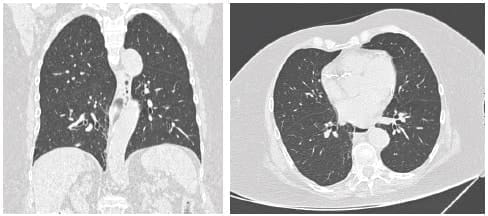

Al encontrarnos cursando el pico de la pandemia, para el ingreso hospitalario, por protocolo se realizó hisopado nasofaríngeo para detección de SARS-CoV2, que fue negativo, y tomografía computarizada de tórax, evidenciando probables imágenes de vidrio deslustrado en base izquierda, compatible con anormalidades consistentes con infecciones diferentes a COVID-19 (CO-RADS 2) (figura 2).

Figura 2. Tomografía de tórax de alta resolución compatible con CO-RADS 2.